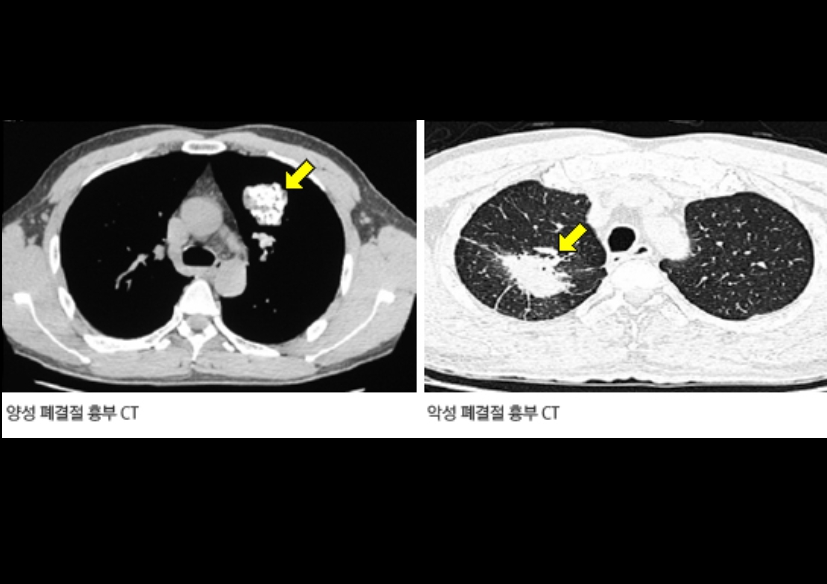

폐 편평세포암은 폐암의 한 유형으로, 주로 흡연과 관련이 있습니다. 기침이 3주 이상 지속되거나 피 섞인 가래, 숨이 차는 증상이 있으면 검사를 받아야 합니다. 흡연자는 비흡연자보다 편평세포암 발생 위험이 몇 배나 높습니다. 금연은 가장 강력한 예방책이며, 폐 건강을 지키는 가장 직접적인 방법입니다.

진단은 흉부 X선, CT, 기관지 내시경, 조직검사로 이뤄집니다. 치료는 수술, 방사선, 항암치료, 면역치료가 병합됩니다. 최근에는 맞춤형 치료제가 도입되어 생존율이 향상되고 있습니다.